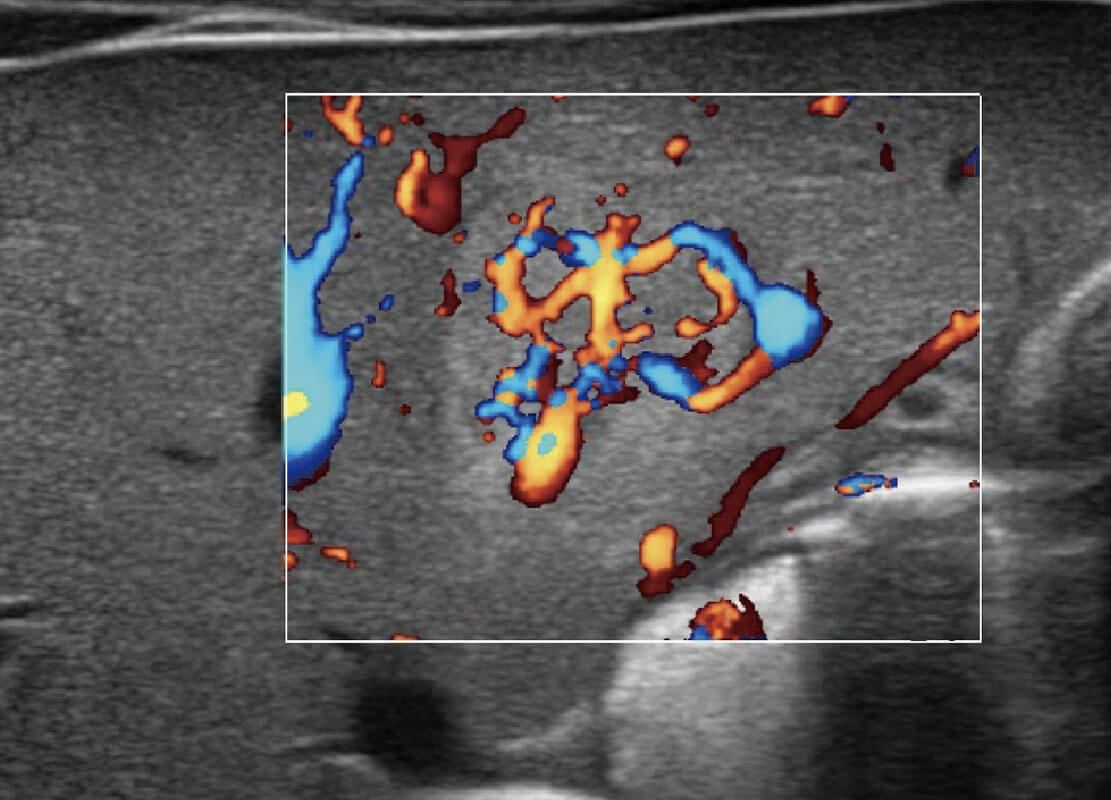

乳腺超声 / 新生儿

P60搭载宽频带线阵探头、宽景成像、弹性成像技术,为您提供乳腺应用方案。P60支持高频相控阵探头、线阵探头、腹部高频探头、腹部微凸探头等,丰富的探头群搭载敏感的彩色血流成像,适用于新生儿多种脏器检测要求,满足新生儿筛查需求。

• 乳腺癌显微血流